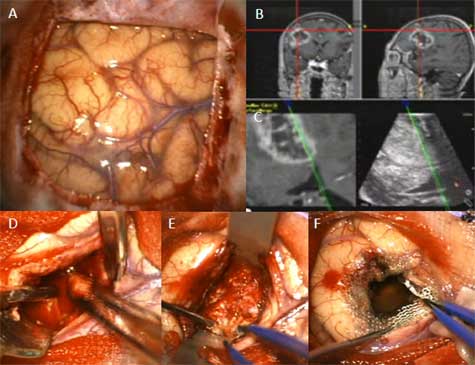

私の目的は、「アメリカの医療器具」を買うのでなく、「日本製の医療器具」を新しくたくさん現場で開発してアメリカに売り込むことだったので、「私の特許」もたくさんタダであげたので一緒にアメリカに行き、「心臓移植手術」や「脳の手術」のお手伝いをして大成功しました。

Doctor doing heart operation. heart transplant operation